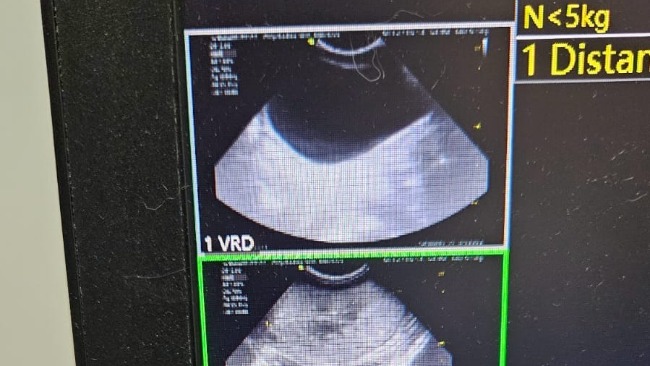

PNN czyli przewlekła niewydolność nerek.

Nieuleczalna. Nerki na usg w złym stanie.

Mocznik,kreatynina parametry bardzo przekroczone. Poza tym jest nieźle.